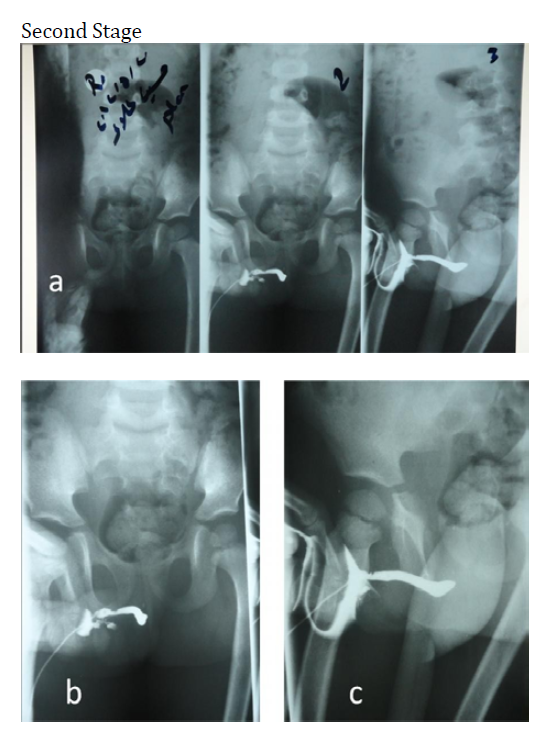

Second Stage

Interval: After an approximate interval of 4-6 months from the first stage, the second stage of the procedure was initiated

Anesthesia and Assessment: Similar to the first stage, patients were administered general anesthesia, and a comprehensive assessment was performed. This included re-evaluation of chordee and meatal dilatation as needed

Meatal Reconstruction: Meatal reconstruction was the first step in the second stage, followed by tubularization of the urethra

Skin Reconstruction: In non-circumcised patients, the skin envelope was mobilized to cover the suture line. In circumcised or re-operative cases, lateral undermining and the use of a dartos fascia flap were employed to effectively cover the suture line of the neo-urethra

Suture Closure and Drain Placement: Sutures were utilized for the final closure of the glans and penile shaft skin. A drain was introduced for postoperative drainage management

Stent Placement: An N-G tube was secured and used as a stent, which remained in place for several weeks. Calibration of the new urethra was performed for an additional 2 months

Figure 3: The 2nd Stage Steps; A. Show the Quality of the Graft after 5 Months, From The1.St Stage, B. The Formation of the Neo-Urethra by U-Shape Incision, C. The Outer Skin Closure by 4-Flap Z-Plasty, D. 3 Wks after Second Stage